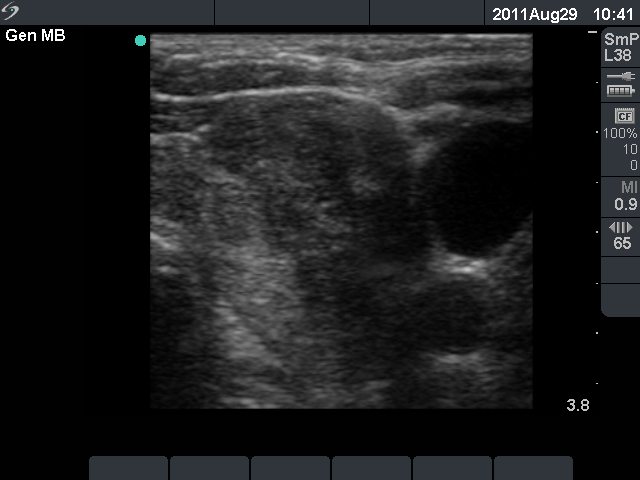

Papillary cancer

Characteristic ultrasound properties - blurred borders of the nodule

The most important sonographic property of a nodule of a papillary carcinoma is the blurred border.